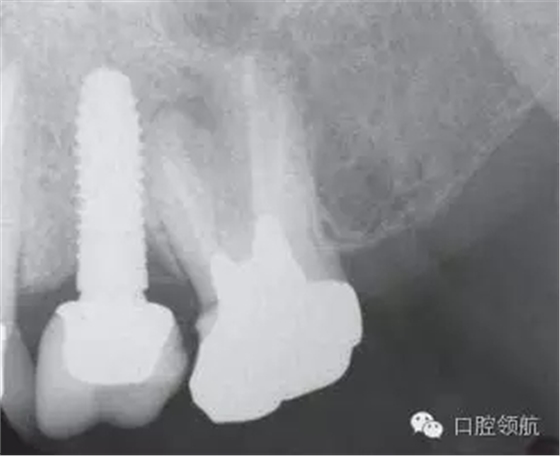

口內(nèi)檢查可見上部修復(fù)體有微動(dòng),沒有發(fā)現(xiàn)周圍黏膜組織的異常(圖1)。 X線影像可以看到種植體的周圍有一定程度的骨吸收但未發(fā)現(xiàn)周圍軟組織的異常(圖2)??紤]是基臺(tái)松動(dòng)的可能性較高。向患者說明松動(dòng)的原因,需要去除上部修復(fù)體后再度擰緊固定基臺(tái)螺絲。因上部修復(fù)體的固定使用的是臨時(shí)粘接劑。先嘗試使用去冠器,但未能去除。

圖2 X線攝影像上可以看到種植體的周圍有一定程度的骨吸收但未發(fā)現(xiàn)有周圍軟組織的異常(圖2)。考慮基臺(tái)松動(dòng)的可能性較高。